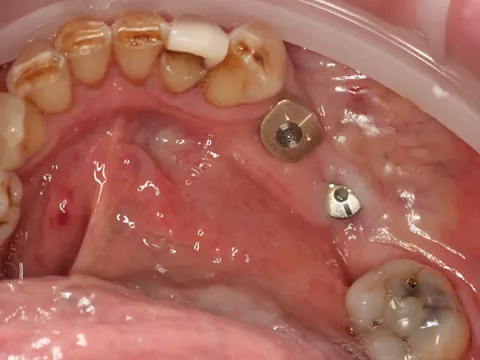

7. Distal implant placed with a cover screw, and mesial implant restored with a HealFit® SH anatomical healing abutment.

7

Suturing was adapted to each implant site. The distal implant was fully submerged with a cover screw, requiring complete primary closure. At the mesial implant, where a HealFit® SH abutment was placed, only two simple interrupted sutures were placed mesially and distally to stabilize the soft tissues.

8. Suturing was adapted to each implant site. The distal implant was fully submerged with a cover screw, requiring complete primary closure. At the mesial implant, where a HealFit® SH abutment was placed, only two simple interrupted sutures were placed mesially and distally to stabilize the soft tissues.